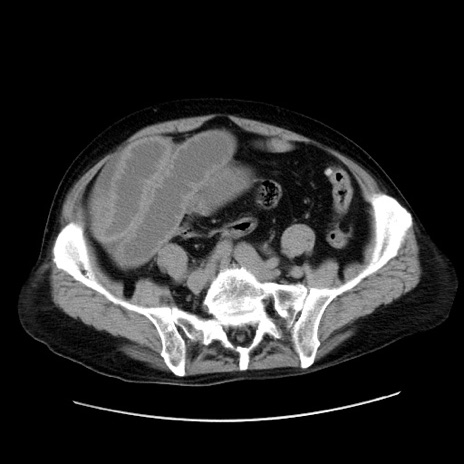

症例30(横断像)

【症例】80歳代男性

【主訴】臍周囲痛

【現病歴】約6時間前から臍下部痛が出現。次第に腹部膨隆・背部痛も生じてきたため来院。背部痛の場所は変化しない。

【身体所見】意識清明、BT 36.3℃、BP  131/87mmHg、P 87bpm、SpO2 100%(RA)、臍周囲自発痛・圧痛あり、反跳痛なし、自発痛部位に一致して板状硬あり、腹部膨隆、腸雑音減弱、CVA tenderness両側陰性。